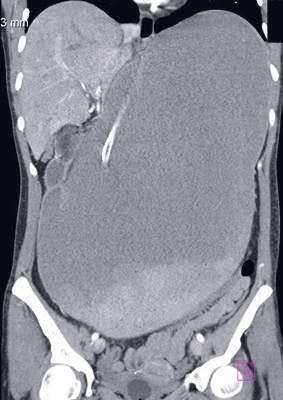

94 Akútne brucho ako príčina smrti pri náhlych úmrtiach

MUDr. Arpád Panyko, PhD., MPH